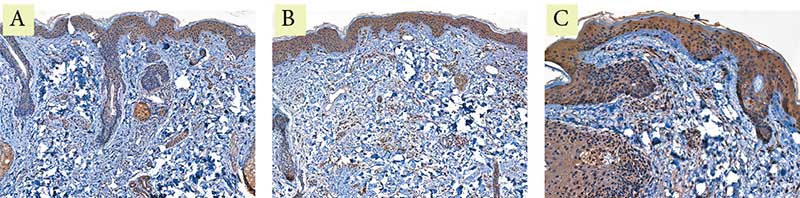

Рис. 5. Пациентка Л. Экспрессия маркера коллагена III типа: A – до процедуры; B – через месяц после процедуры; C – через пять месяцев после процедуры